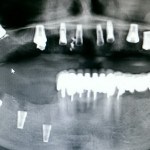

Ну и, совсем нонсенс, когда челюстно-лицевые хирурги в стационаре промышляют имплантацией. И ладно бы, если у них там есть ортопед, либо пациент направляется в стационар с уже готовым планом протезирования, имплантации, с хирургическими шаблонами и пр… Увы, но по мнению некоторых челюстно-лицевых хирургов, главное — это захренячить куда-нибудь импланты. А далее ортопед разберется, что на них делать.